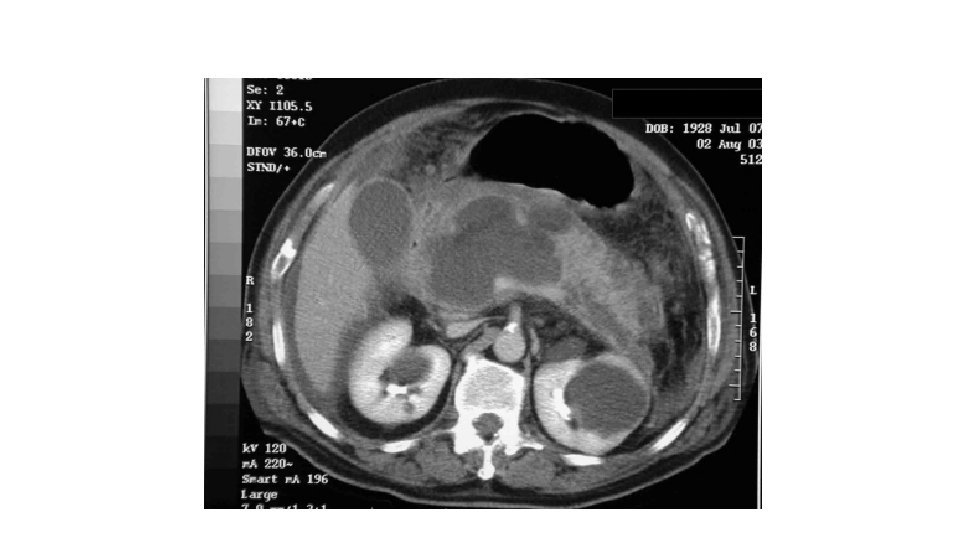

CT Scan of acute pancreatitis • CT shows significant swelling and inflammation of the pancreas

CT features • Pancreatic atrophy, calcifications, and main pancreatic duct dilation 56